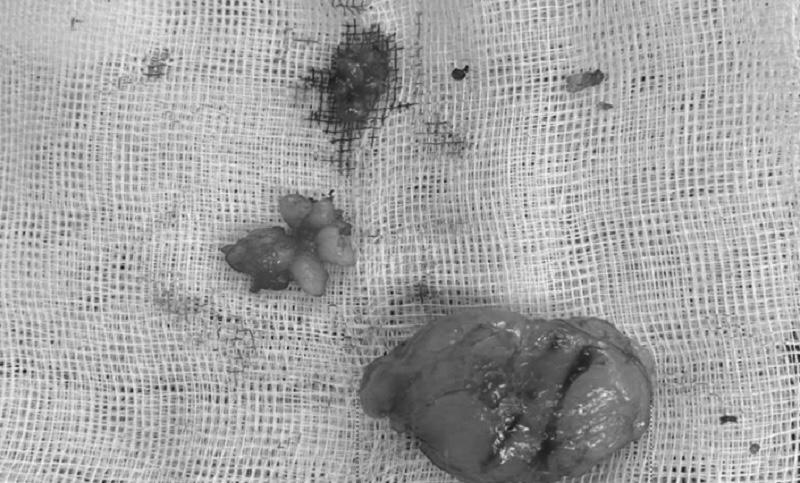

Khối u của bệnh nhân đã được phẫu thuật loại bỏ. Ảnh: BVCC

Sau khi phẫu thuật lấy toàn bộ khối u, bệnh phẩm được gửi mẫu đến Trung tâm Giải phẫu bệnh để thực hiện xét nghiệm mô bệnh học và hóa mô miễn dịch. Kết quả cho thấy, hình ảnh phù hợp với u xơ đơn độc (solitary fibrous tumor) – một loại u mô mềm hiếm gặp.

Tiên lượng bệnh nhân sau phẫu thuật tốt vì khối u ít có nguy cơ biến đổi ác tính. Khối u giới hạn rõ, chưa xâm nhập phá vỡ vỏ u trên đại thể/ vi thể; tỷ lệ nhân chia (phân bào) thấp < 4/10 HPF và không có hoại tử.